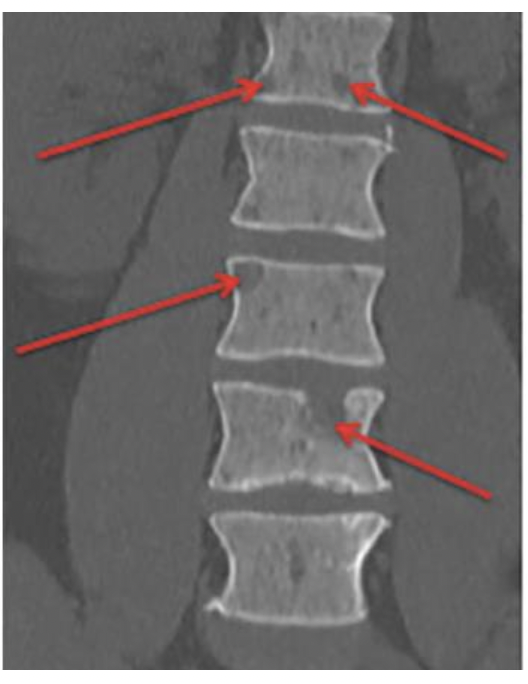

Bone lesions

הדמיה- לראות שהם לא מפתחים נגעים בעצמות.

אם יש יותר ממצא אחד של נגע בעצמות זה כבר נקרא מיאלומה פעילה.

שני נגעים פוקאליים